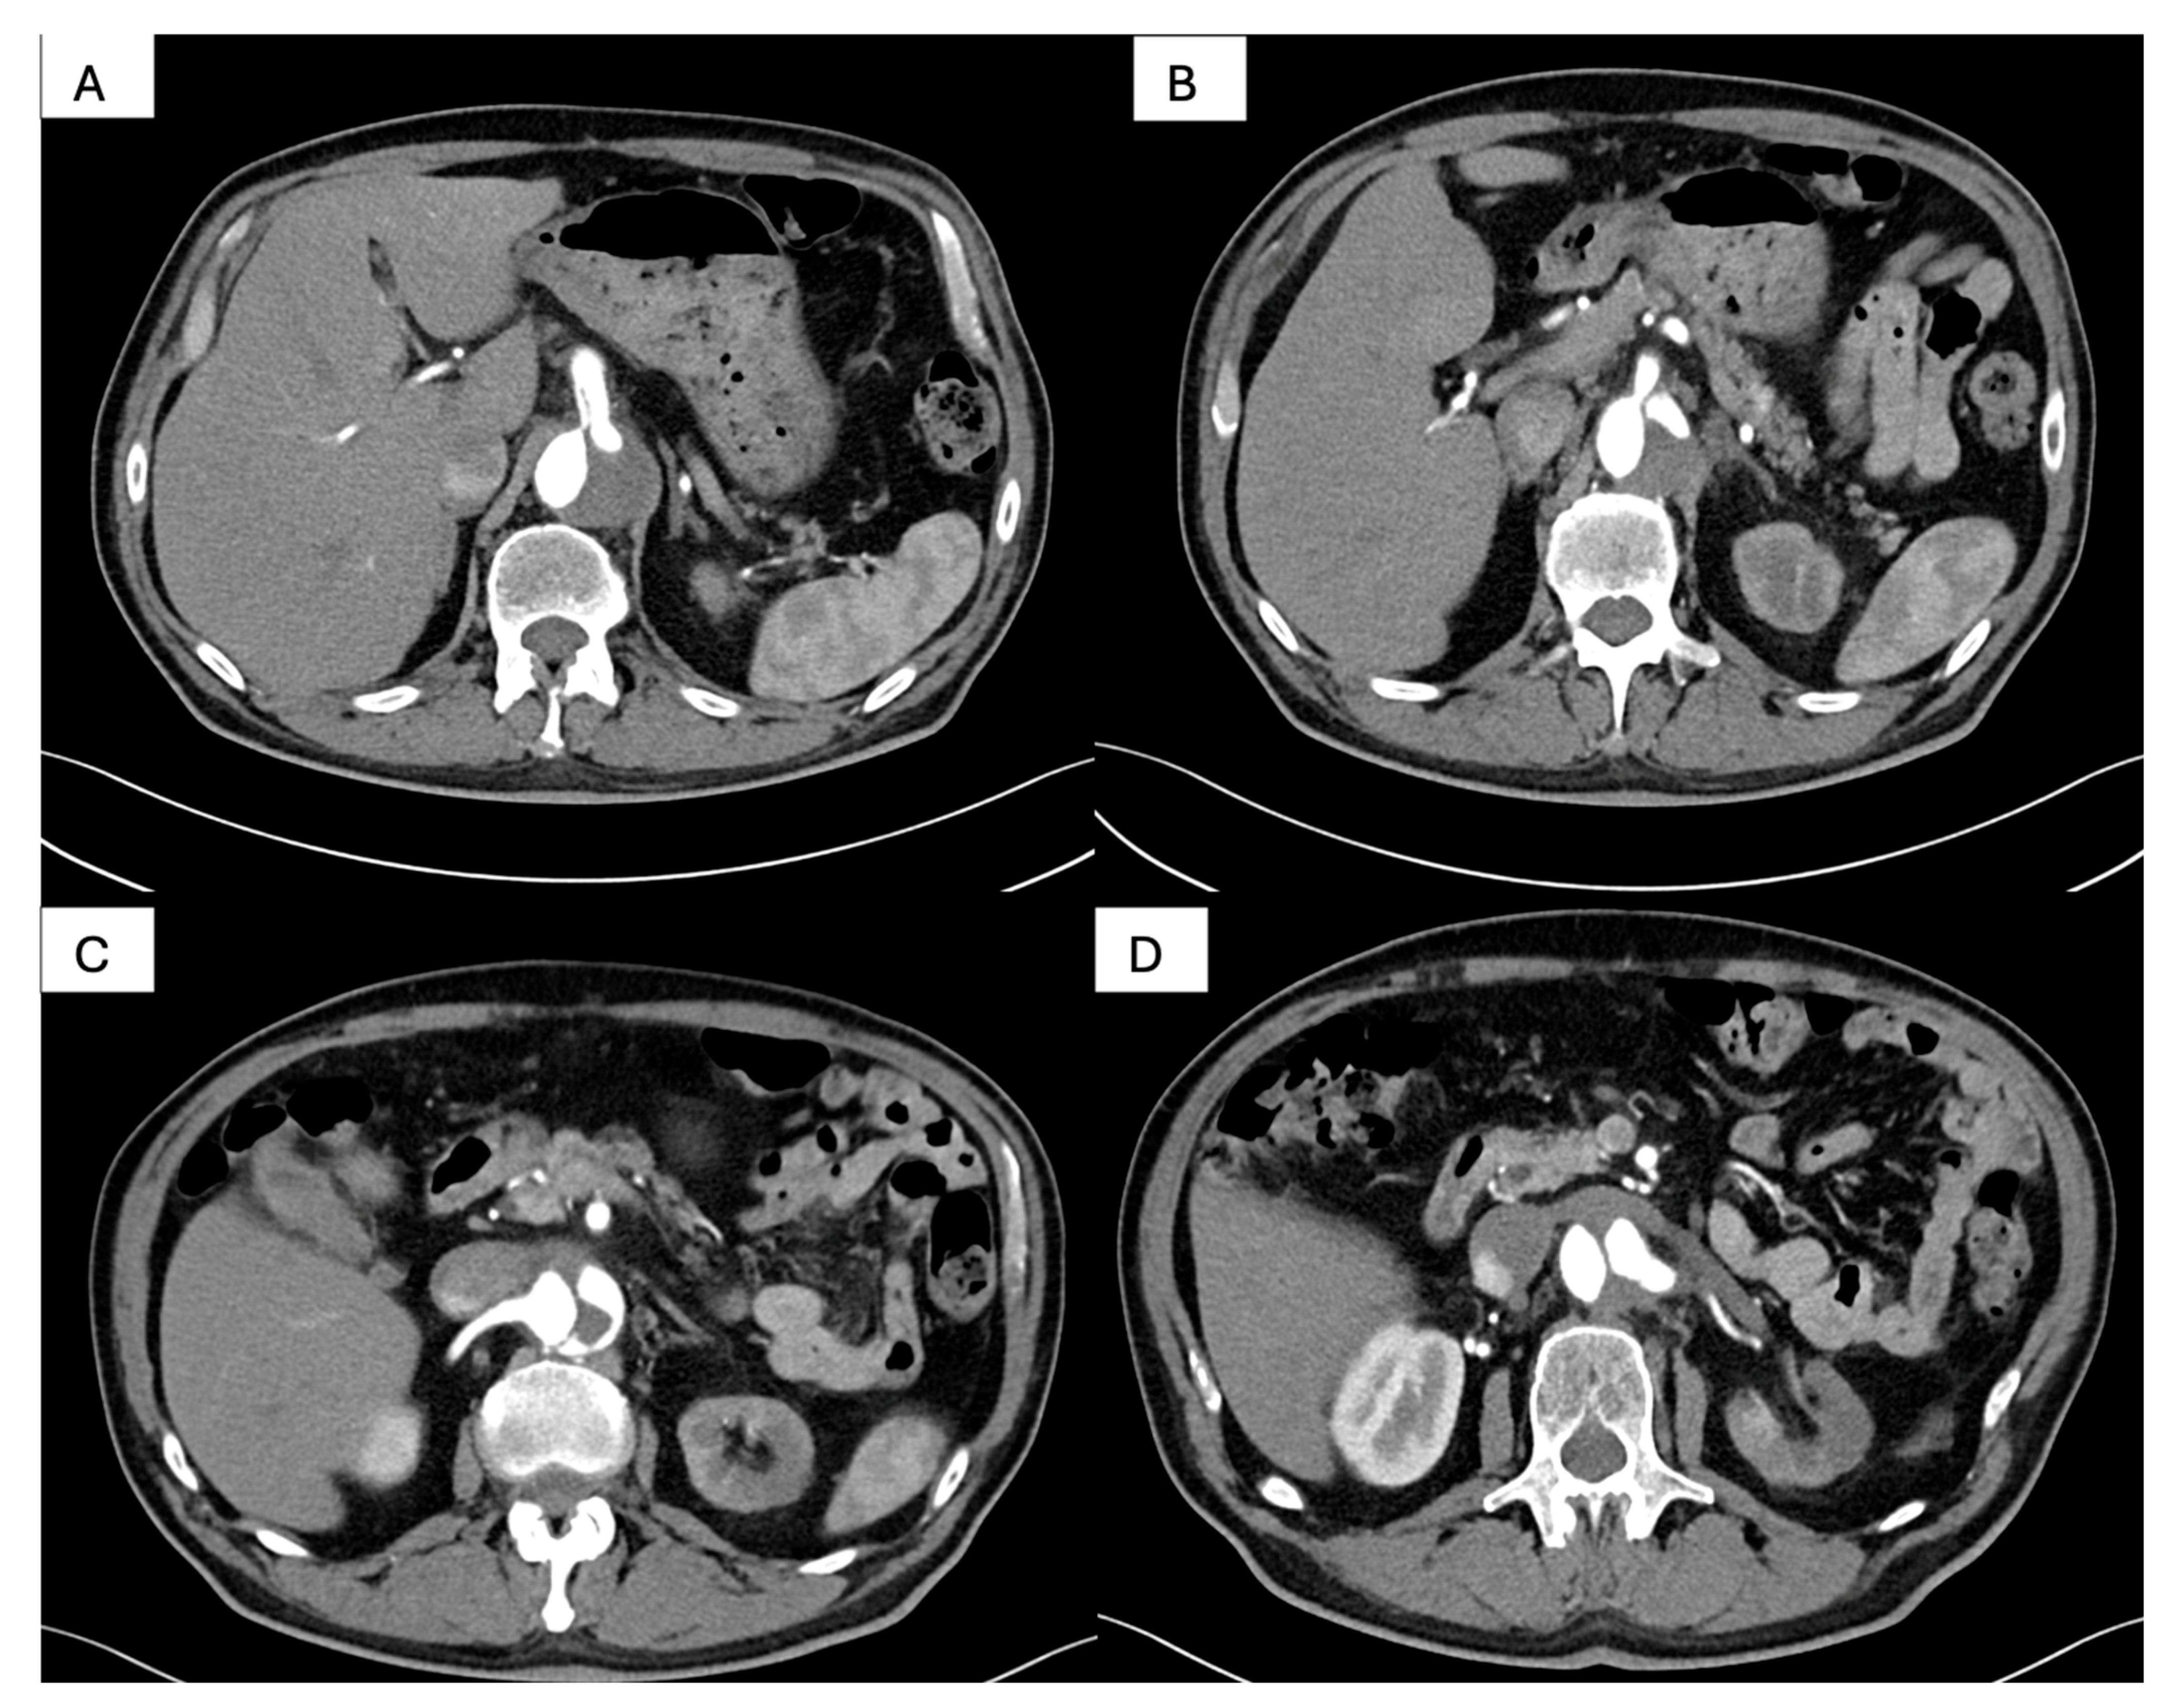

| True lumen | Severely compressed along descending thoracic and abdominal aorta | Re-expanded across thoracic segment | Stable re-expansion |

| Visceral perfusion | SMA and celiac from severely collapsed TL; R renal from FL | TL restored at visceral segment; R renal improved inflow | Full visceral patency; no endoleak |